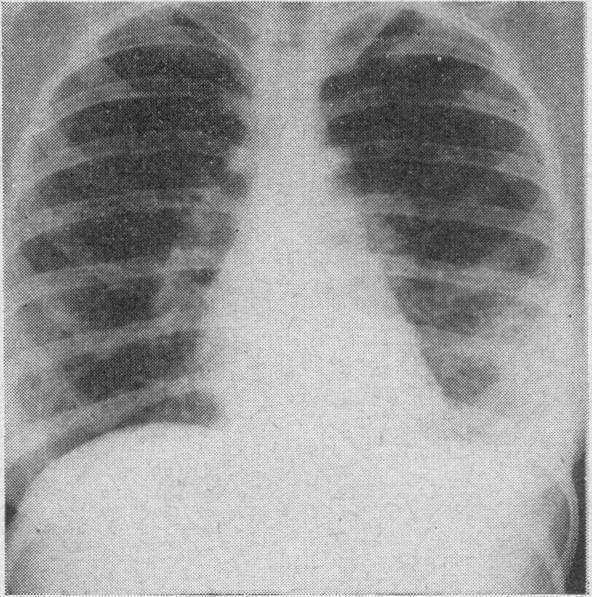

BLOOM J, RUBIN J H

Can Med Assoc J. 1950 Oct;63(4):355-7.